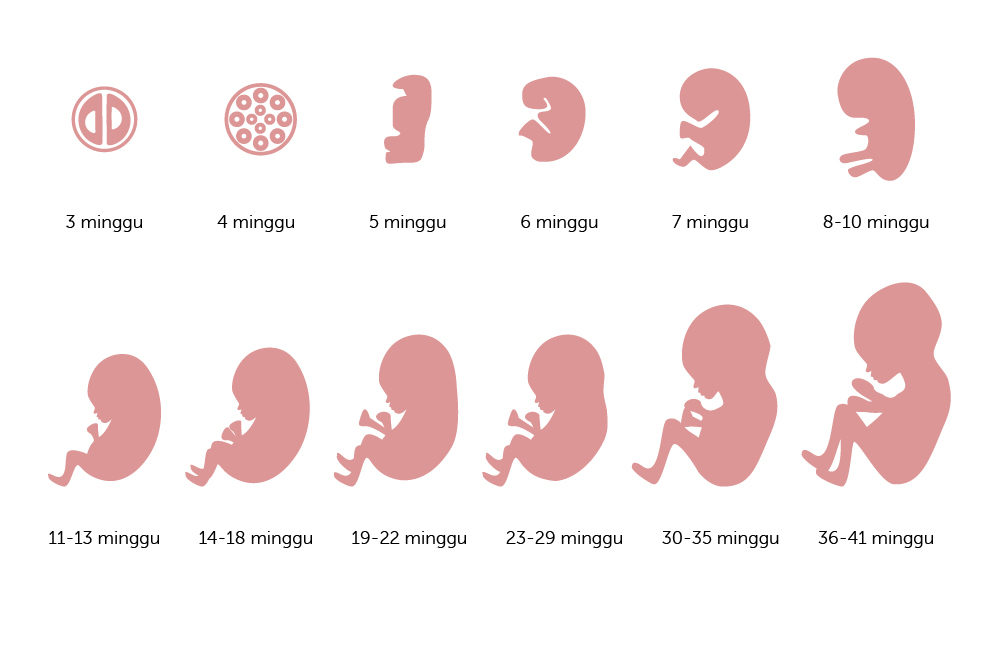

Perkembangan Janin Minggu Ke Minggu 1 40 Gambar Lengkap

Perkembangan Janin Minggu Ke Minggu 1 40 Gambar Lengkap

Perkembangan Janin Minggu Ke Minggu 1 40 Gambar Lengkap

Perkembangan Janin Minggu Ke Minggu 1 40 Gambar Lengkap

Ini Perkembangan Bayi Dalam Kandungan Dari Minggu Ke Minggu Alodokter

Ini Perkembangan Bayi Dalam Kandungan Dari Minggu Ke Minggu Alodokter

Perhatikan Tahap Kehamilan Dan Perubahan Yang Dilalui Ibu Hamil Berikut Ini Alodokter

Perhatikan Tahap Kehamilan Dan Perubahan Yang Dilalui Ibu Hamil Berikut Ini Alodokter

Perhatikan Tahap Kehamilan Dan Perubahan Yang Dilalui Ibu Hamil Berikut Ini Alodokter

Perhatikan Tahap Kehamilan Dan Perubahan Yang Dilalui Ibu Hamil Berikut Ini Alodokter

Ini Perkembangan Bayi Dalam Kandungan Dari Minggu Ke Minggu Alodokter

Ini Perkembangan Bayi Dalam Kandungan Dari Minggu Ke Minggu Alodokter